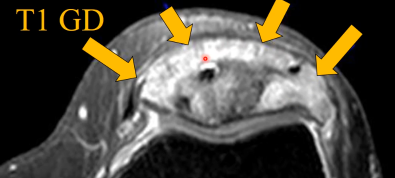

IRM

- Hyperémie locale (Se voit dans l’ensemble en scintigraphie)

- Préservation de composante graisseuse dans les zones touchées

- Zones plus actives = moelle en hyper T2